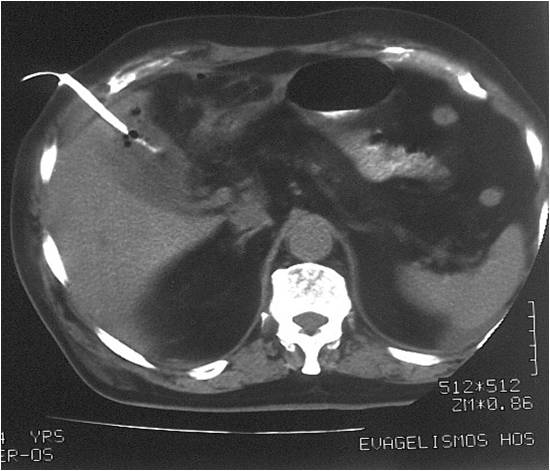

- Abscess post left hemicolectomy

- Successful placement and drainage